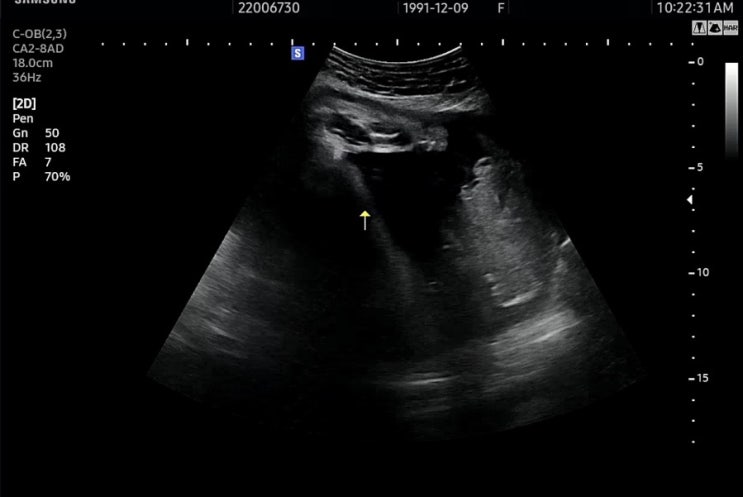

[36w1d] 산본제일병원 태동검사, 출산 전 마지막 진료(제왕절개 수술 동의서 작성 외)

막달이어서 일주일마다 병원 방문 중! 이전 방문시에는 막달검사(혈액, 소변, 엑스레이, 심전도 등)를 받았...